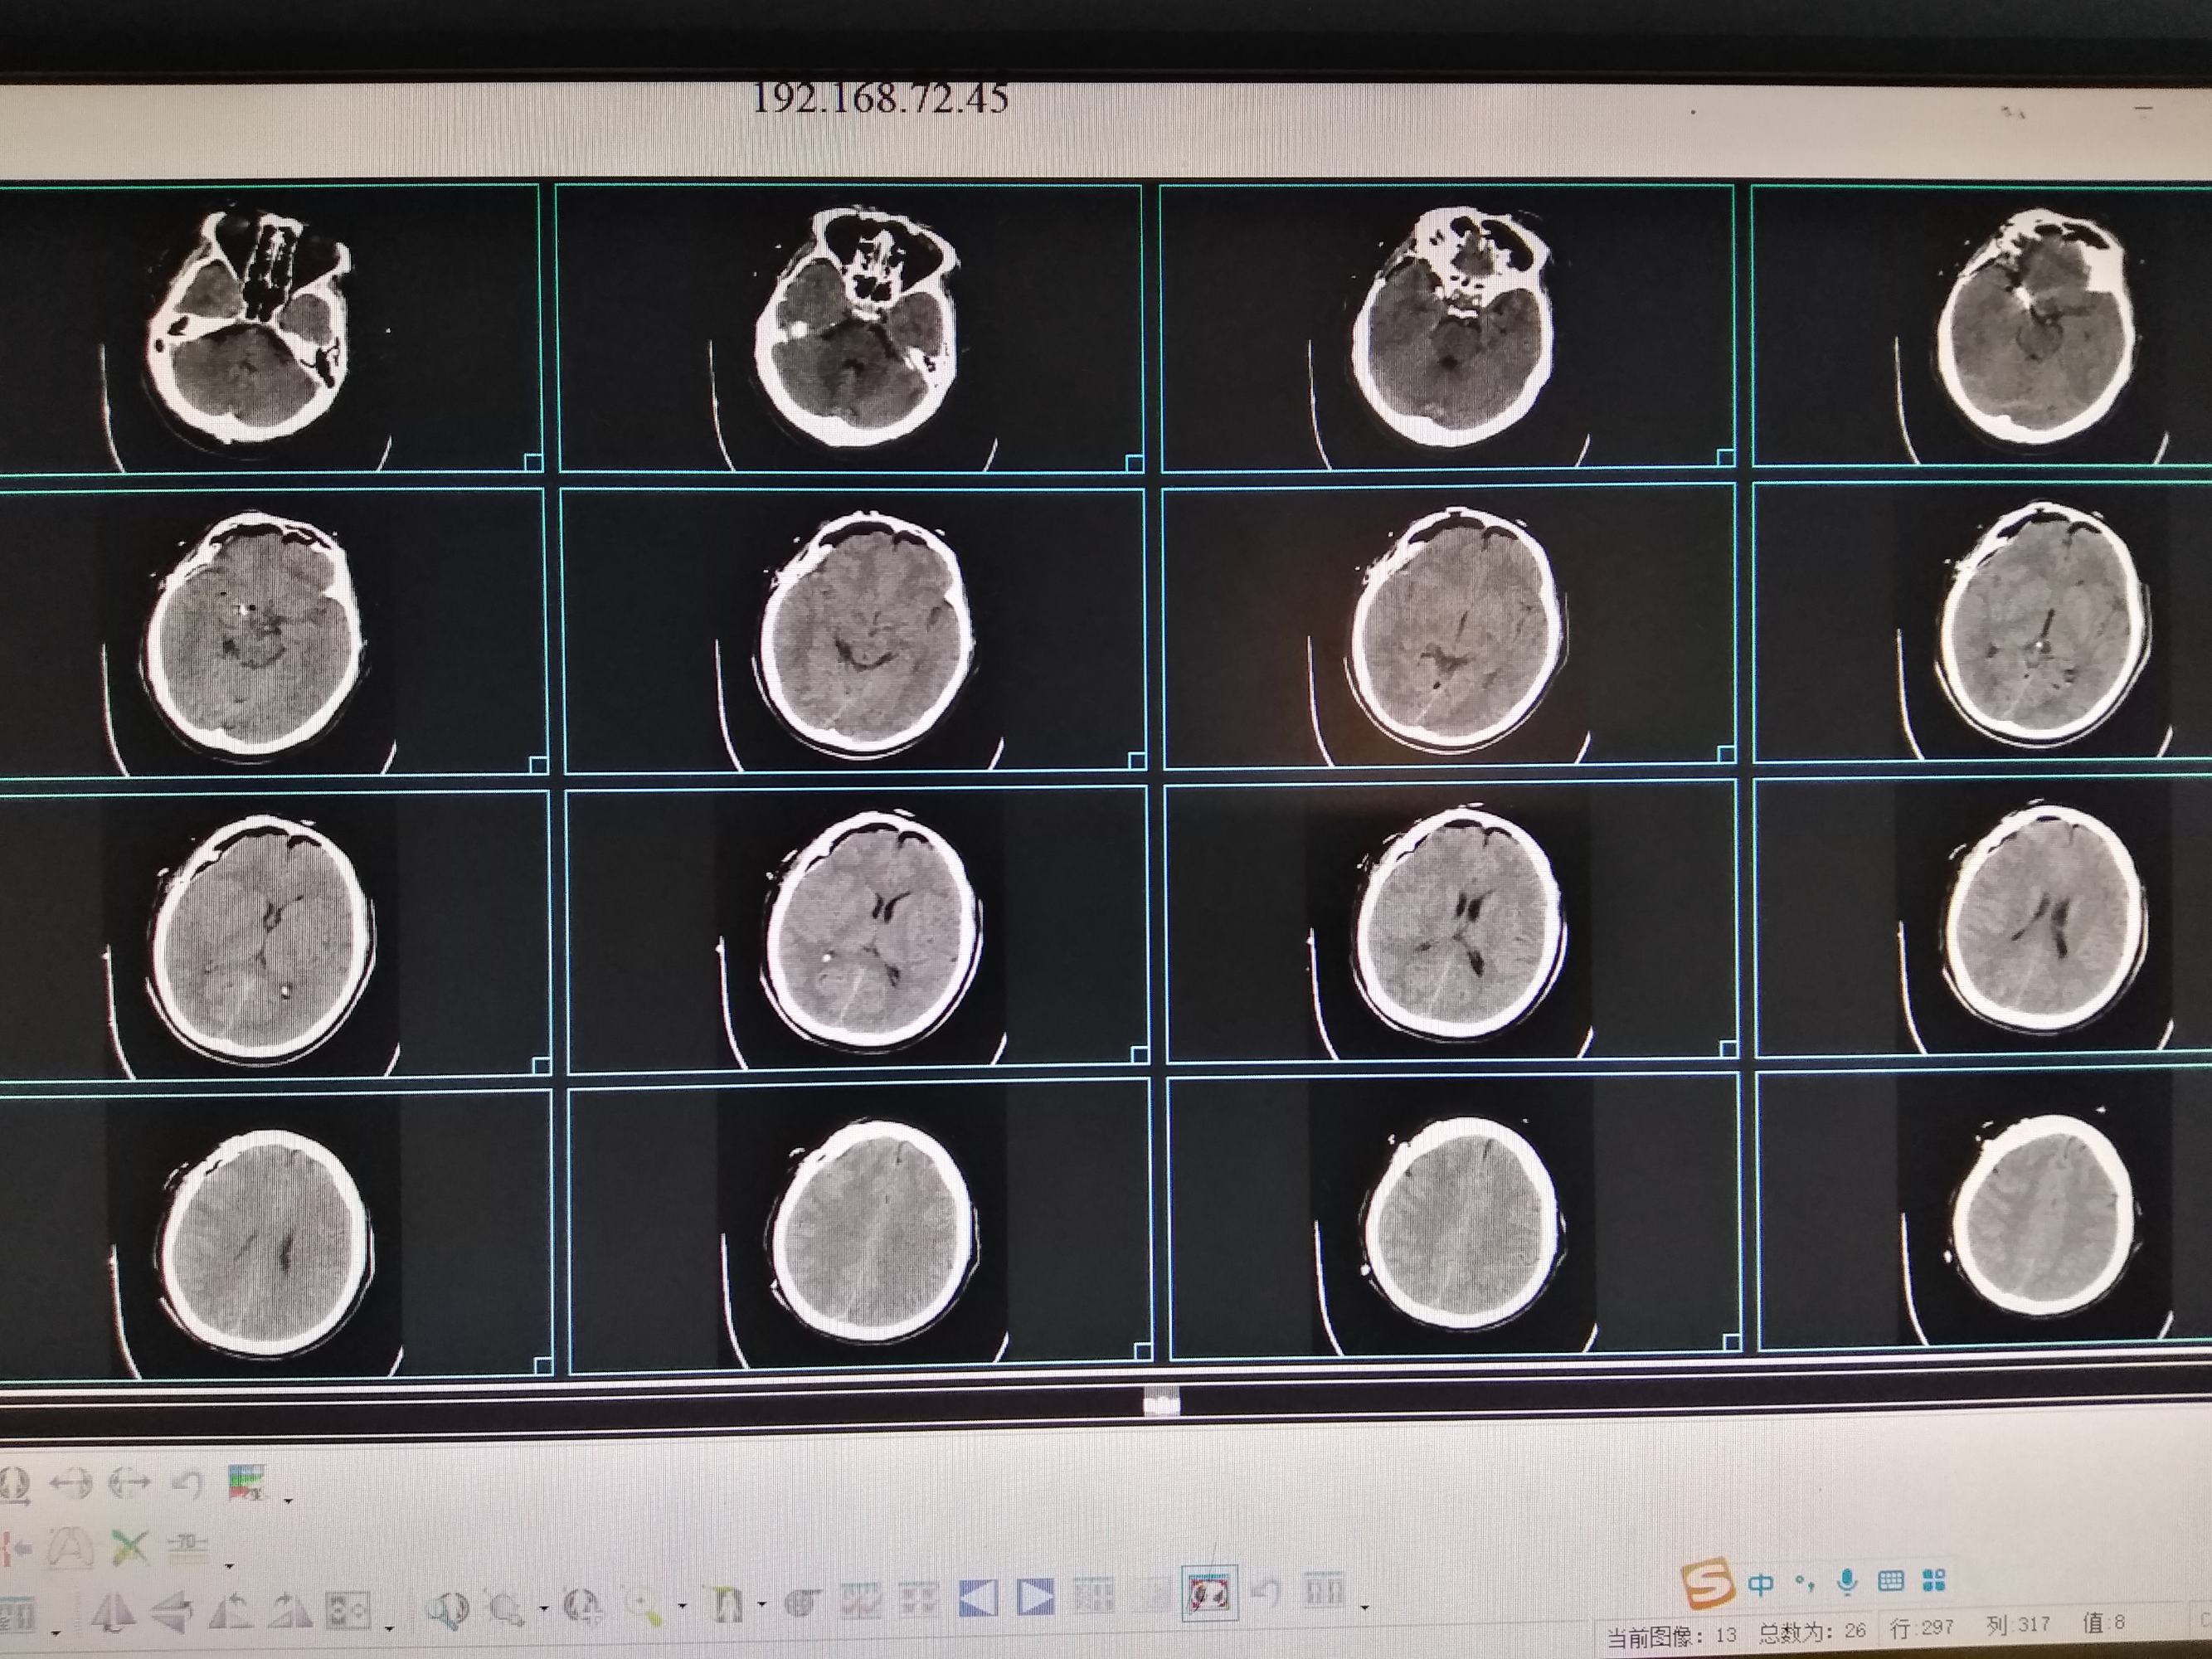

50岁男性患者,突发头疼一天入院,头颅CT检查提示蛛网膜下腔出血

术后顺利清醒,言语肢体活动正常,复查头颅CT满意